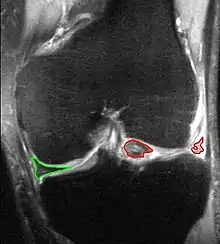

يُمكن استخدام صور الأشعة السينية (عادة خلال حَمل ثقل) لاستبعاد أي حالة أخرى، ولمعرفة ما إذا كان لدى المريض أيضا هشاشة عظام، ولا يمكن رؤية الغضاريف الهلاليَّة ذاتها بالتصوير الإشعاعي العادي، وإذا لم يكن التشخيص واضحًا من أخذ التاريخ الطبي والفحص، فيمكن تصوير الغضروفين الهلالييّن بالرنين المغناطيسي، وحلت هذه التقنية مكان تصوير المفصل السابق الذي يتضمن حقن مادة تباين داخل المفصل، وفي الحالات الواضحة يوفر تنظير مفصل الركبة تشخيصًا سريعًا وعلاجًا في وقت واحد، وتُظهر البيانات السريريَّة الحديثة أن التصوير بالرنين المغناطيسي والاختبارات السريريَّة متشابهة في الحساسيَّة والنوعيَّة عند البحث عن تمزق في الغضروف الهلالي.

ويُمكن تصنيف هذه التمزقات أيضًا من ناحية قربها لإمدادات الدم للغضروف الهلالي؛ أي من حيث وقوعها في المناطق "أحمر- أحمر"، أو "أحمر- أبيض"، أو "أبيض- أبيض".

لكن تكمن الأهمية الوظيفية لهذه التصنيفات -في نهاية المطاف- في تحديد ما إذا كان الغضروف الهلالي قابل للإصلاح، وتعتمد قابليَّة إصلاح الغضروف الهلالي على عدد من العوامل التي تتضمن: